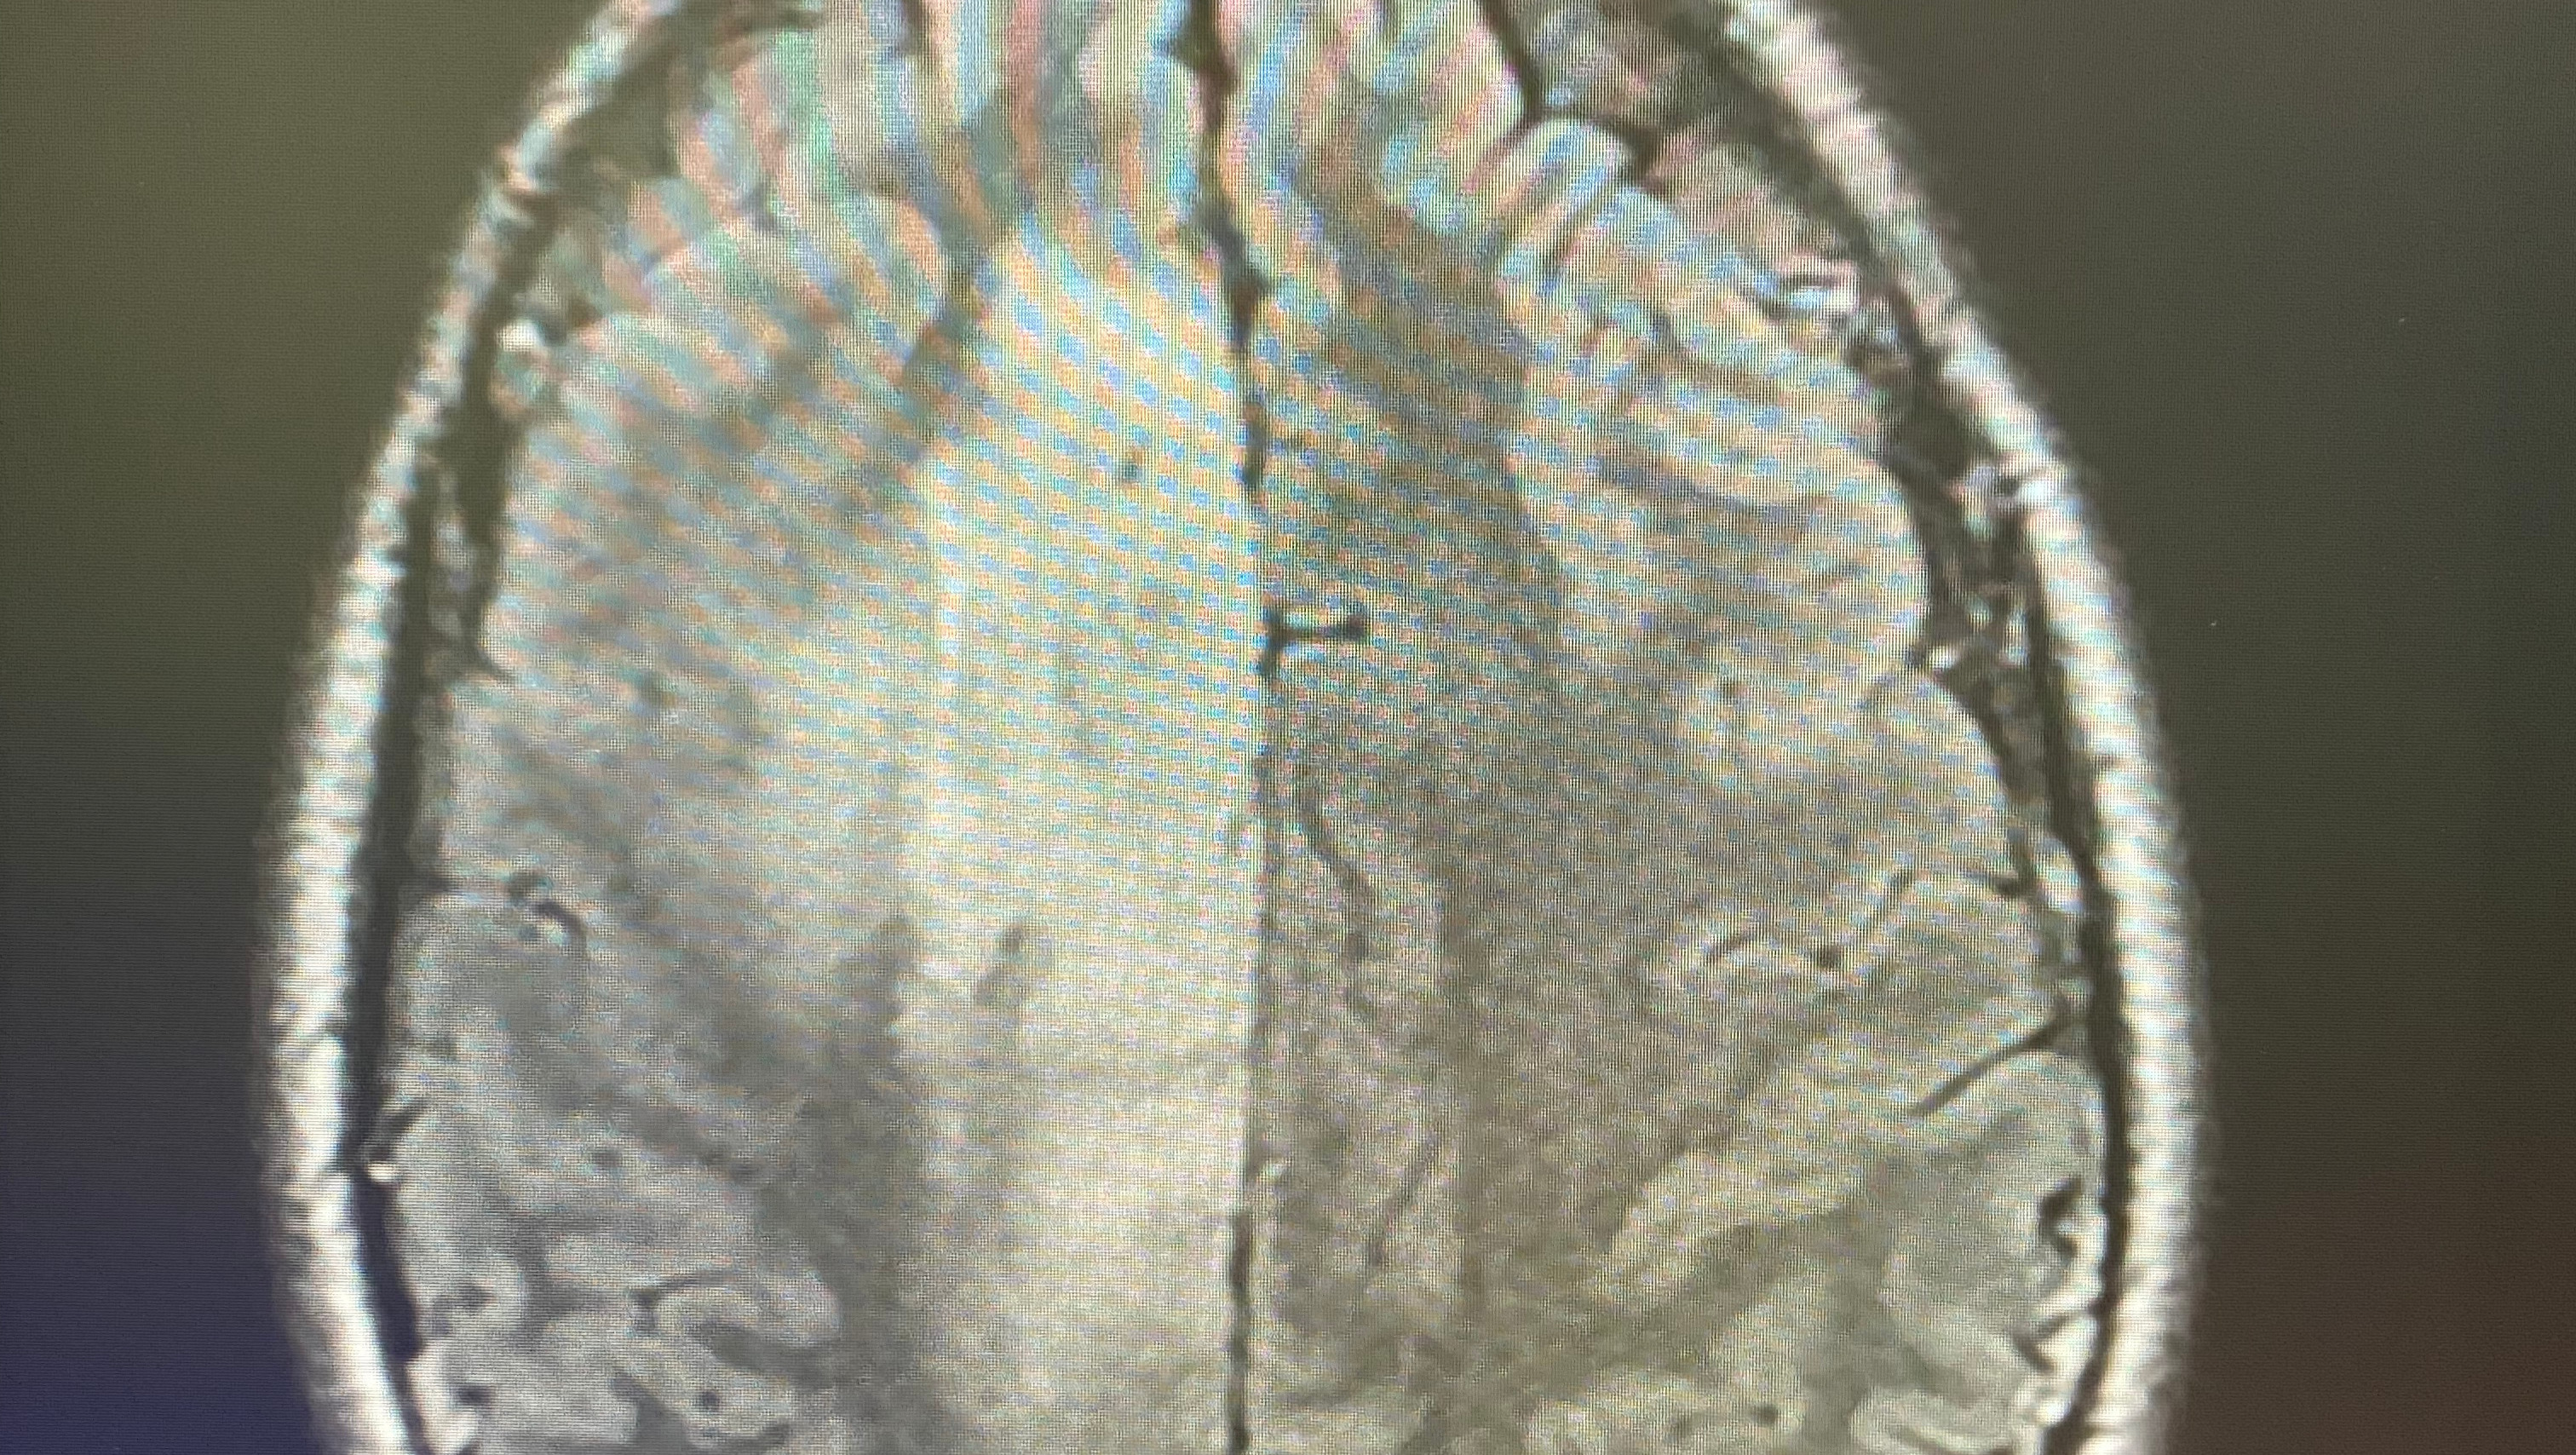

On Friday, Feb. 25, Dillon Reichel will undergo surgery to remove a stage 2-3 glioma brain tumor.

While sleeping on Jan. 18, Dillon experienced a grand mal seizure which woke his fiancee Vynessa. She provided care until paramedics arrived and rushed Dillon to the emergency room. There, doctors discovered the mass in his brain.

Dillon’s surgery, an awake craniotomy with the goal of removing as much of the tumor as possible, will be performed at Penn Medicine Brain Tumor Center in Philadelphia under the care of Dr. Nduka Amankulor, a leading cancer immunobiologist. Doctors will analyze the removed tissue to determine the tumor’s aggressiveness and plan the next steps in treatment. Dr. Amankulor has instructed Dillon to expect radiation or chemotherapy to further eradicate the tumor.